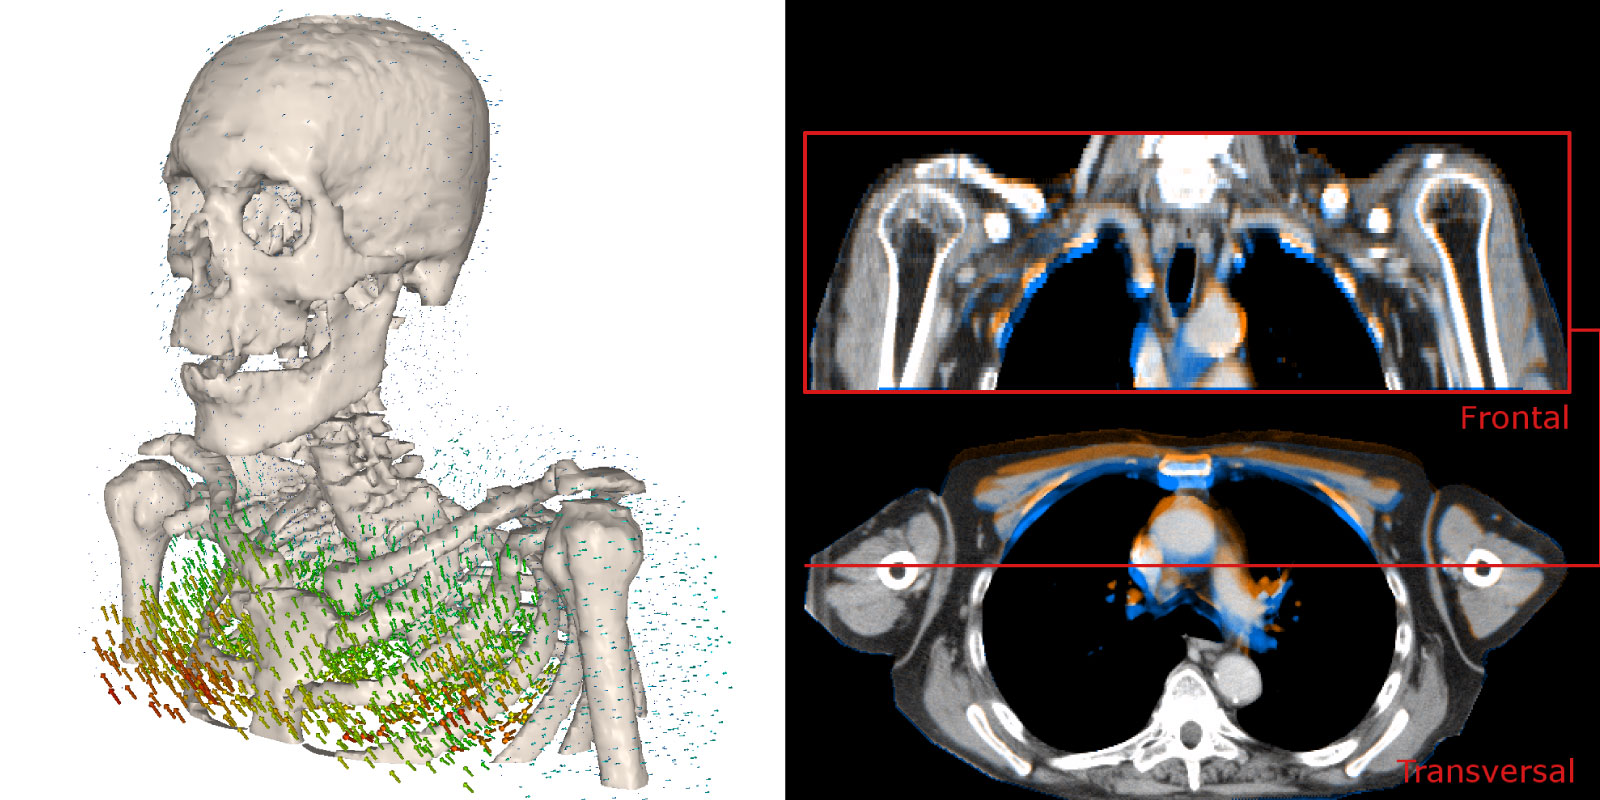

Composite medical visualization showing two related views of human anatomy. On the left, a 3D rendering of a human skeleton (skull, spine, ribs, and shoulders) with numerous colored vectors or arrows around the chest and rib cage indicating motion or force directions. On the right, two CT scan slices of the upper chest: a frontal view at the top and a transverse (cross-sectional) view at the bottom, with colored overlays highlighting anatomical structures around the lungs, heart, and shoulder area.

Modern radiotherapy can deliver radiation with remarkable precision. However, in areas such as the thorax, breathing motion causes tumors and surrounding organs to move in complex ways, making accurate imaging and dose delivery more challenging.

In a new blog post on the Helmholtz Imaging CONNECT platform, Richard Häcker explores how these challenges affect adaptive radiotherapy and the evaluation of medical image registration methods. Using lung radiotherapy as an example, the article highlights how even small misalignments between CT and MRI scans can influence dose calculations and biomarker analysis.